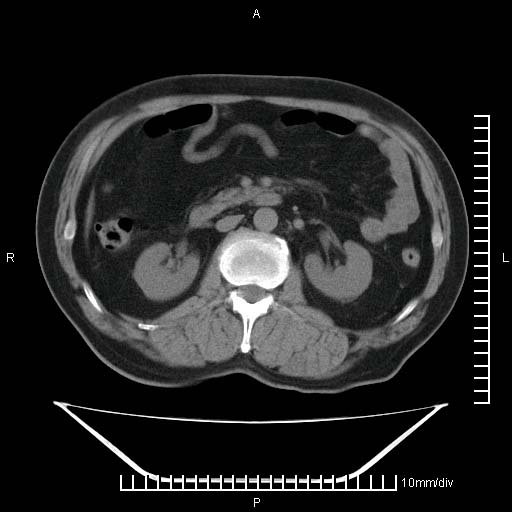

标题: CT25082:肝脏增强:男性,70岁 [打印本页]

标题: CT25082:肝脏增强:男性,70岁

患者以心脏疾病收住院,腹部无明显症状,b超查肝脏有占位。

增强效果不理想。考虑转移,胆囊壁明显增厚,不排除胆囊癌肝转移。

牛眼征,中心坏死无强化,外缘强化,最外缘又见低密度,考虑转移,与脓肿鉴别

肝内多发转移瘤,右下肺炎症并少量胸水。胃壁增厚建议胃镜,胰尾部“病变”为肠管。

1)肝脏多发性转移瘤(不排除胰尾癌转移所致可能)。2)腹水。3)右侧少量胸腔积液。

ct25082 结果:转移瘤

外院mr结果:胰尾恶性占位。